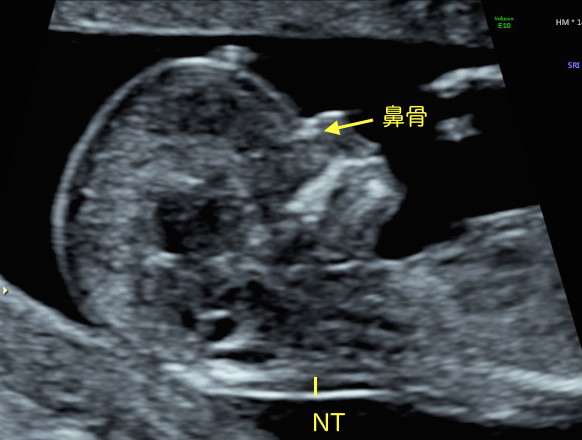

- QNTとは何ですか?

- ANTとは、英語のNuchal Translucency の頭文字をとったものです。妊娠10〜14週ころの赤ちゃんの首や頭の後ろにある、透けて見える部分のことを言います。「首の後ろのむくみ」などと表現されることが多いですが、全ての赤ちゃんに見られる現象で、これは病的な状態ではありません。皮下にリンパ液がたまって見えるだけで、リンパ管が発達していくにつれて消失していきます。

病的なNTを評価するためには、超音波検査によって一定の条件の下で正確な測定が重要であり、通常の妊婦健診では行っていません。なぜなら、たった0.5mmの測定の違いが診断精度を18%も下げると言われているからです。日本ではNT専門の技術認定資格がなく、英国胎児医学財団Fetal Medicine Foundationなどの技術認定資格をもった医師が行う必要があります。また、NT値が正常であっても病気があることがあり、他の観察事項(心拍数・鼻骨・心臓内および心臓への血流など)や、初期血清マーカー検査(PAPP-A、freeβhCG)と組み合わせて、最終的にリスクを推定します。